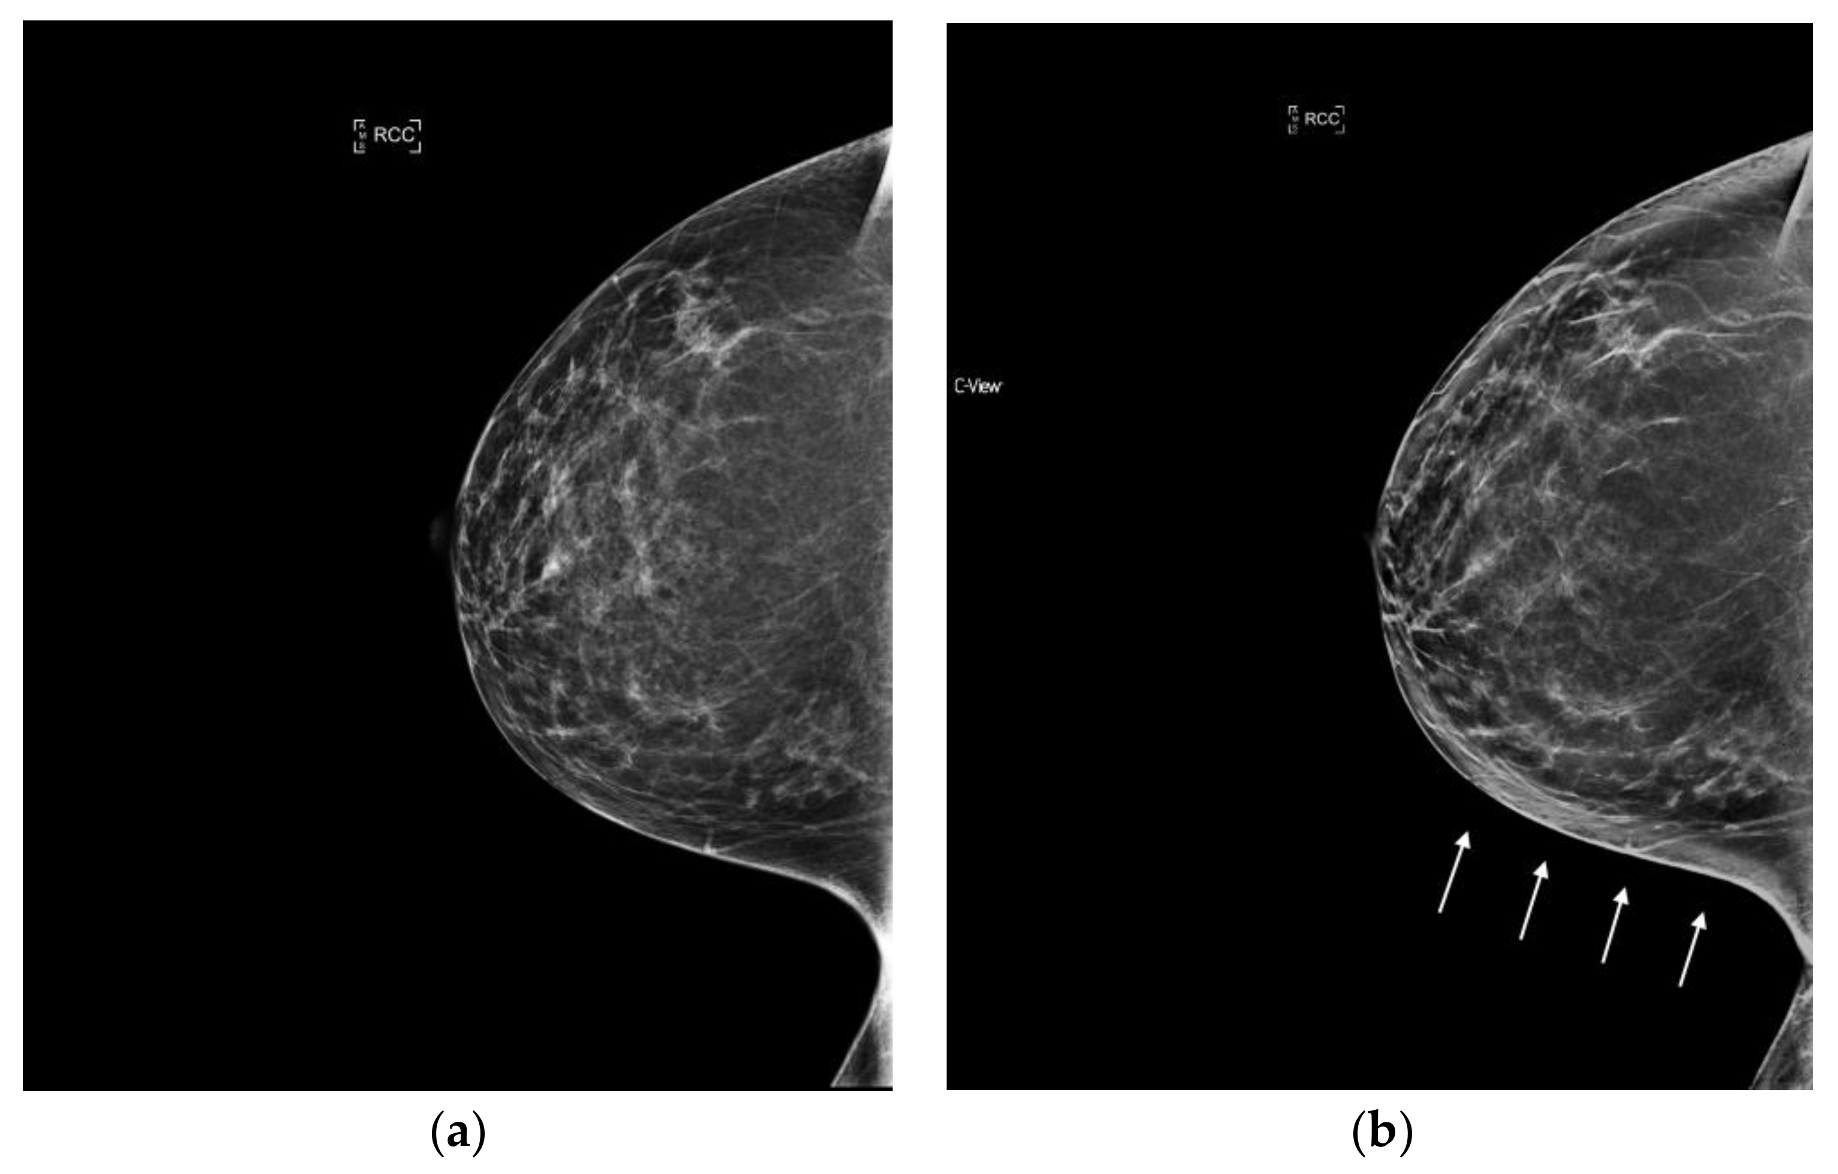

6.3. Architectural Distortion

The reconstruction algorithm’s enhancement of line structures can also emphasize the appearance of architectural distortions (AD). Taken together with the ability of tomosynthesis to clear away superimposed tissue, s2D+DBT can permit confident identification of subtle cancers presenting as AD. (Figure 3).

Figure 3.

Architectural Distortion (circled in black) detected on screening mammogram with synthesized mammography and confirmed on tomosynthesis images (slices shown here), permitting confident Breast Imaging Reporting and Data System (BIRADS) 0 assessment. After diagnostic work-up and biopsy, pathology confirmed well-differentiated invasive ductal carcinoma, ER/PR+, Her2-, with grade 1 ductal carcinoma in situ. (a) s2D CC (b) DBT slice CC (c) s2D mediolateral oblique (d) DBT slice mediolateral oblique.

Giess et al. showed architectural distortions were significantly more conspicuous on synthesized mammography compared to FFDM (p < 0.001) [39]. Indeed, Mariscotti et al. found poor concordance in classification of AD between s2D and 2D FFDM (κ = 0.36), with six malignant ADs missed on 2D FFDM [33]. As s2D is derived from the DBT dataset, it may retain more information on tissue structure from the multiple projection images compared to 2D FFDM, emphasizing mammographic findings like AD.

Freer et al. reported no significant change in recall rates for AD with synthesized mammography [31]. This may reflect that AD characterization is best defined by tomosynthesis images, rather than by 2D or synthesized 2D.

It is important to note that normal ligaments may also be enhanced and present as possible distortions. As with calcifications, confirmation in both planes and with tomosynthesis can avoid false positive recalls. Careful diagnostic work-up and wariness of distortions that “spot away” remains prudent, given the high probability of malignancy of ADs. Additional studies could explore whether use of s2D increases detection of benign radial scars/complex sclerosing lesions, which may also present as AD.